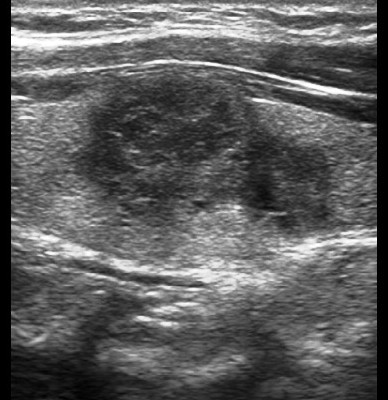

Case 2 : Thyroid Malignancy

A 27 year female complained of swelling in left side neck and it notably increased over a period of 6 months.

Ultrasound Images:

Ultrasound features of a malignant thyroid nodule : solid, hypoechoic irregular margins, absence of a hypoechoic halo around the nodule.

Hypoechoic lesions have a higher risk of being malignant. Lymphadenopathy and local invasion of adjacent structures are highly specific features of thyroid malignancy but are less commonly seen.